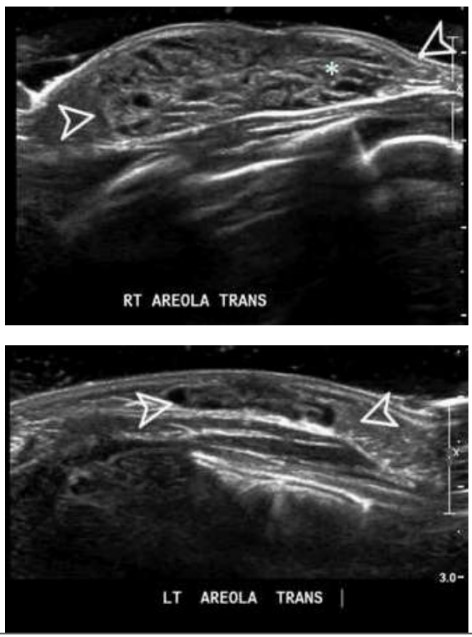

Analise o caso a seguir.

Recém-nascida (RN) do sexo feminino, com 10 dias de vida é levada ao consultório com aumento unilateral da mama direita, sem outras queixas (vide abaixo). A mãe nega comorbidades clinicas ou alterações durante a gestação e o parto.

A conduta recomendada para esse caso é a